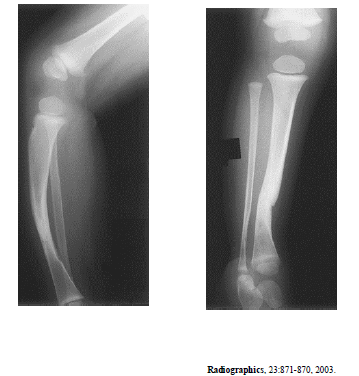

A radiografia acima é de um paciente do sexo masculino, com 25 anos de idade, com queixa de dores no joelho. Considerando essa imagem, é correto afirmar que

o diagnóstico mais provável é de tumor de células gigantes.

a lesão situa-se na medular.